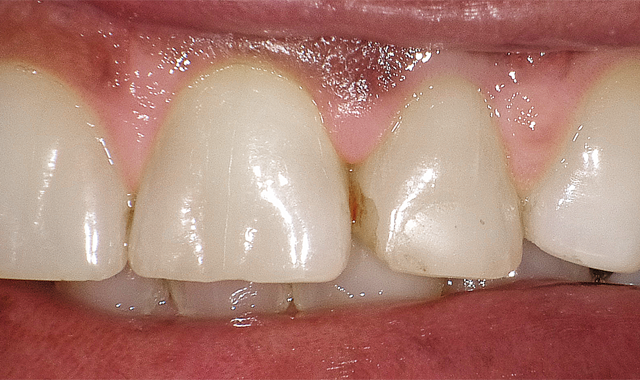

After the layering was completed, a series of disks were utilized (Fig. 6) for finishing and polishing.

After the layering has been completed, a series of disks are utilized for finishing and polishing.

Fig. 7 shows the chameleon effect of G-ænial Sculpt. The great results led to congratulations going out to GC America in receiving The Catapult Vote of Confidence for G-ænialTM Sculpt.

The chameleon effect of G-aenial Sculpt is illustrated here.